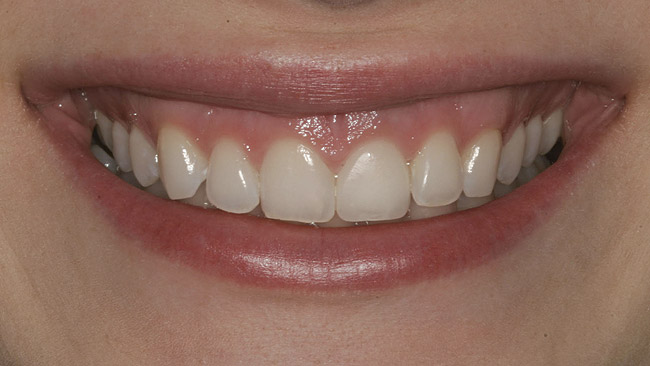

Figure 1  Initial presentation with yellow, poorly color-matched restored mandibular anterior teeth.

Figure 1

Figure 8  Full smile—finished feldspathic crowns on teeth Nos. 22, 23, 27, and 28; implant crowns in sites 24 through 26; esthetic harmonization with opposing dentition.

Figure 8